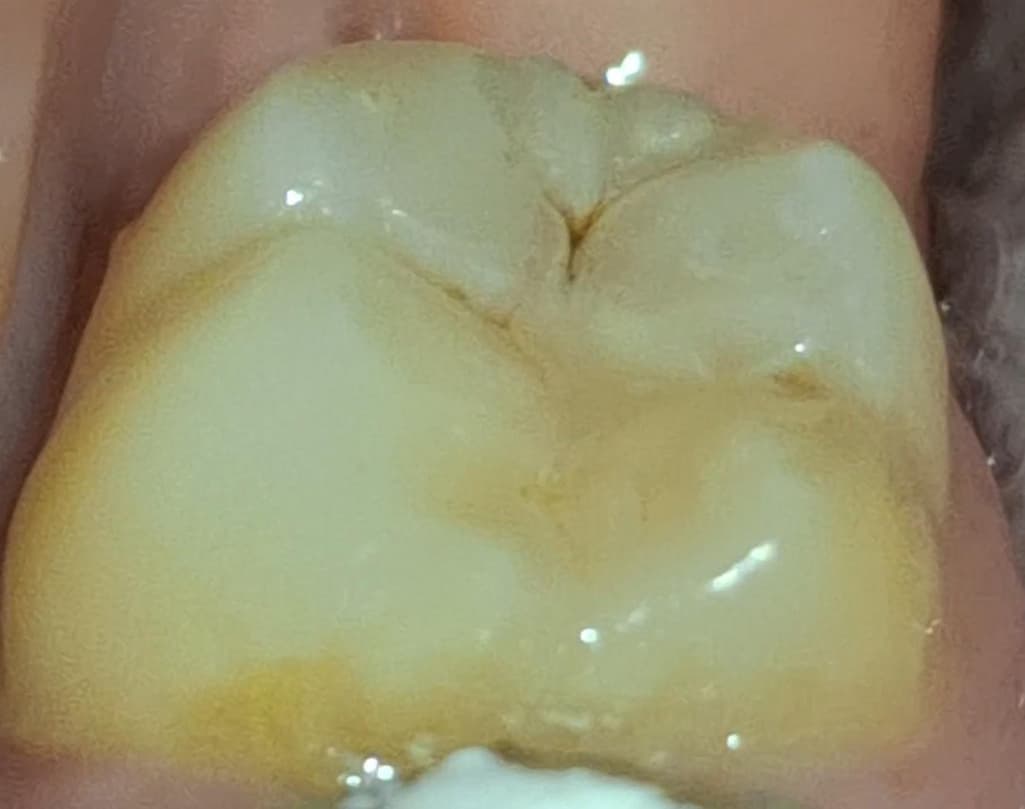

7월 초에 레진한 곳 옆부분이 조금 벗겨졌는데 .. 충치같은 게 보여서요.

두번 째 ,세 번째 사진은 어제 찍은 사진이에요.)

빨간 동그라미 부분 첨이랑 달리 조금 벗겨졌는데.. 검갈색에 자국이 보여서요.

사진상으로는 잘 안보여도 실제로 보면 더 잘보여요 ㅠㅠ

제가 궁금한 부분은 레진 벗겨진 곳에 갈색 자국이 있어도 되는건가요? 저것도 정지우식이라서 그냥 레진으로 덮으신걸까요?

사진에 상에 보이는 충치는 치료를 해야될것같으니 치과에 가셔서 검진후 치료를 받으시는게 좋을것같습니다.

사진으로 봤을 떄에는 정지우식같아 보이기는 합니다만 벗겨졌다면 재치료 받으시면 됩니다.

사진으로 봤을 경우에는 치아에 홈이 생긴 것으로 보입니다. 치아에 홈이 생기게 되면 대부의 이물질이 들어가게 되어 충치가 더 커질수 있습니다. 이런 경우 홈이 있는 부분을 메꿔주는 것이 좋을 수 있습니다.

빨간원 안쪽도 그렇고 그 옆쪽도 아직 충치가 있어보입니다 치과가서 해당 부위 전반적으로 다시 봐달라고하세요